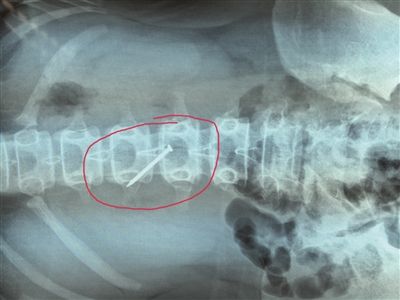

長(zhǎng)約4厘米的鐵釘被取出時(shí),已刺穿13歲女生的胃壁。 朱鼎兆 攝

一根長(zhǎng)近4厘米的鐵釘在胃里會(huì)怎么樣?29日下午4時(shí)許,在淮安市婦幼保健院,該院小兒科醫(yī)生就從宿遷泗陽(yáng)一名13歲女生小軒(化名)的胃里成功取出一根長(zhǎng)約4厘米的鐵釘,而此時(shí),這根鐵釘已經(jīng)刺破了小軒的胃壁。